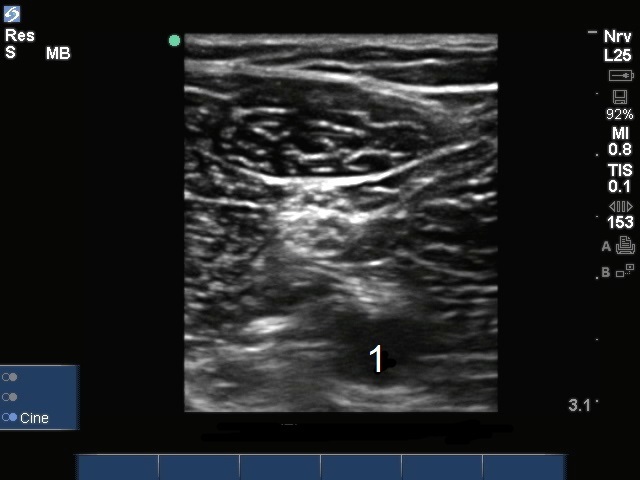

腘神经分叉 1 图像

腘神经分叉

动脉